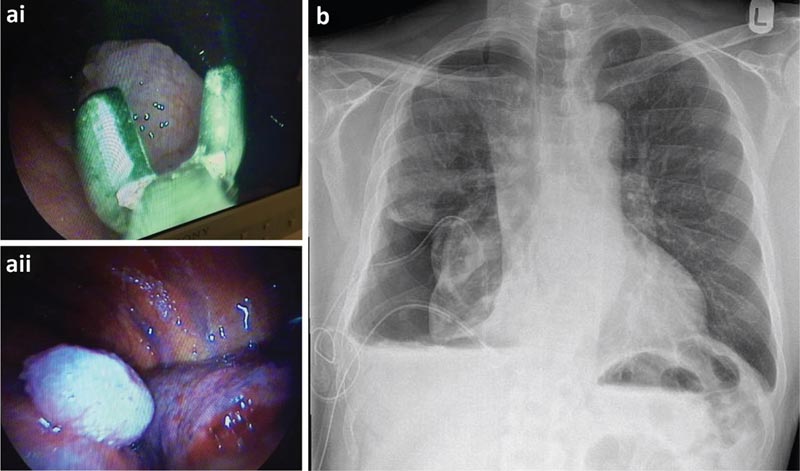

Poiché la citologia del liquido pleurico non era diagnostica, il paziente è stato sottoposto a toracoscopia in anestesia locale e sedazione moderata (TAS), nota anche come toracoscopia medica o pleuroscopia. È una procedura medica eseguita da pneumologi, che comprende l’esame interno, la biopsia e/o la somministrazione di agenti terapeutici nella cavità pleurica.

Il paziente è stato sottoposto a TAS che ha evidenziato un gran numero di noduli sulla pleura viscerale e parietale. Si è deciso di inserire un catetere pleurico a permanenza (PPC) al momento della toracoscopia per un probabile polmone non espandibile.

a) Biopsie della pleura parietale effettuate durante la toracoscopia e visione toracoscopica di un nodulo maligno. b) Radiografia del torace post-toracoscopica.

Le biopsie pleuriche hanno rivelato un mesotelioma epitelioide maligno. Dopo la discussione da parte di un team multidisciplinare, il paziente è stato inviato in oncologia per il trattamento. Il paziente ha continuato a drenare il suo IPC 3 volte a settimana e successivamente ha raggiunto l’autopleurodesi. Il CPP è stato rimosso poco dopo.